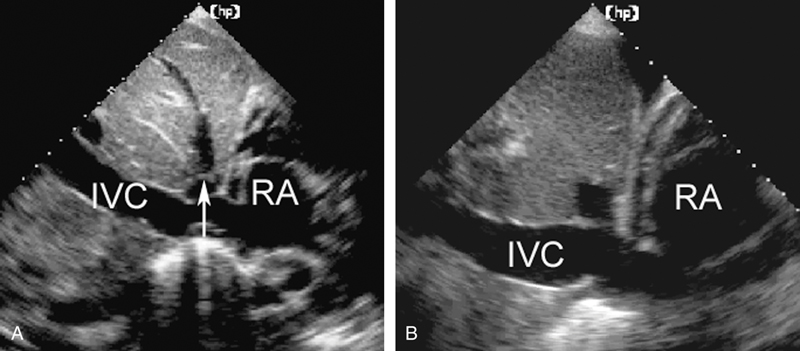

فحوصات تشخيصية لبعض امراض القلب والشرايين التاجية